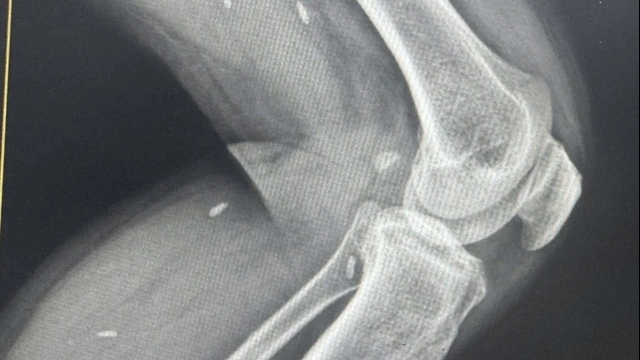

Ngoài ra, bệnh viện cũng đầu tư đồng bộ về cơ sở vật chất cùng trang thiết bị hiện đại hàng đầu thế giới, đến từ hãng Philips (Hà Lan/Mỹ), GE Healthcare (Mỹ), Beckman Coulter (Mỹ), Roche-Hitachi (Nhật Bản), Olympus (Nhật Bản), Nihon Kohden (Nhật Bản),... đảm bảo các tiêu chí về hiệu quả, an toàn, tiết kiệm thời gian, chính xác và thân thiện với môi trường. Hệ thống phòng mổ, phòng phẫu thuật chấn thương chỉnh hình, phòng phẫu thuật phụ sản,... cùng trung tâm nội soi hiện đại, đồng bộ, giúp tối đa hóa hiệu quả chẩn đoán và điều trị.